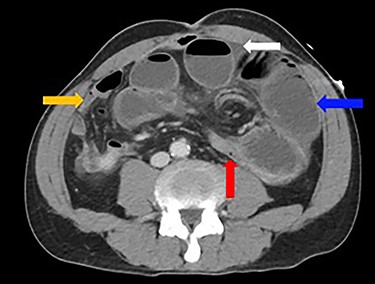

A 52-year-old man presented with a 1-day history of generalized abdominal pain, distension and vomiting. Two years prior, he underwent a subtotal colectomy for colorectal cancer associated with Lynch syndrome and adjuvant chemotherapy. He was haemodynamically stable on presentation. Examination revealed a soft abdomen with marked distension and left periumbilical tenderness, however, no peritonism. Biochemistry showed lactate: 1.9, white cell count: 17 and C-reactive protein: 10. Computed tomography (CT) abdomen demonstrated a closed-loop SBO with transition point mid-abdomen, free fluid but no free gas (Figs 1 and 2). The patient was resuscitated with intravenous fluids, a nasogastric tube was inserted and they proceeded to an exploratory laparotomy for the closed-loop SBO. Intra-operative findings noted a loop of distended small bowel adherent to the anterior abdominal and pelvis side walls, with a loop of ileum twisted at the mesentery secondary to a band adhesion causing the closed-loop obstruction. The patient underwent adhesiolysis and untwisting of the mesentery, which demonstrated viable ileum with no evidence of perforation. In addition, the liver was smooth, there was no evidence of peritoneal metastases and the previous side-to-side ileo-sigmoid anastomosis was intact with no evidence of stricture or cancer recurrence. Lastly, milky intra-abdominal fluid was noted intra-operatively, with a sample sent for biochemistry showing a triglyceride level of 1584 mg/dl indicative of CA. Post-operative recovery was delayed by a prolonged ileus for which they were commenced on total parenteral nutrition (TPN) and slowly upgraded to a low-fat diet following resolution of the ileus. They were discharged home on Day 49 post-operatively.

Dilated loops of small bowel (blue arrow), oedematous mesentery (suggestive of closed-loop obstruction; red arrow), free fluid (evidence of CA; white arrow) and collapsed small bowel (orange arrow)